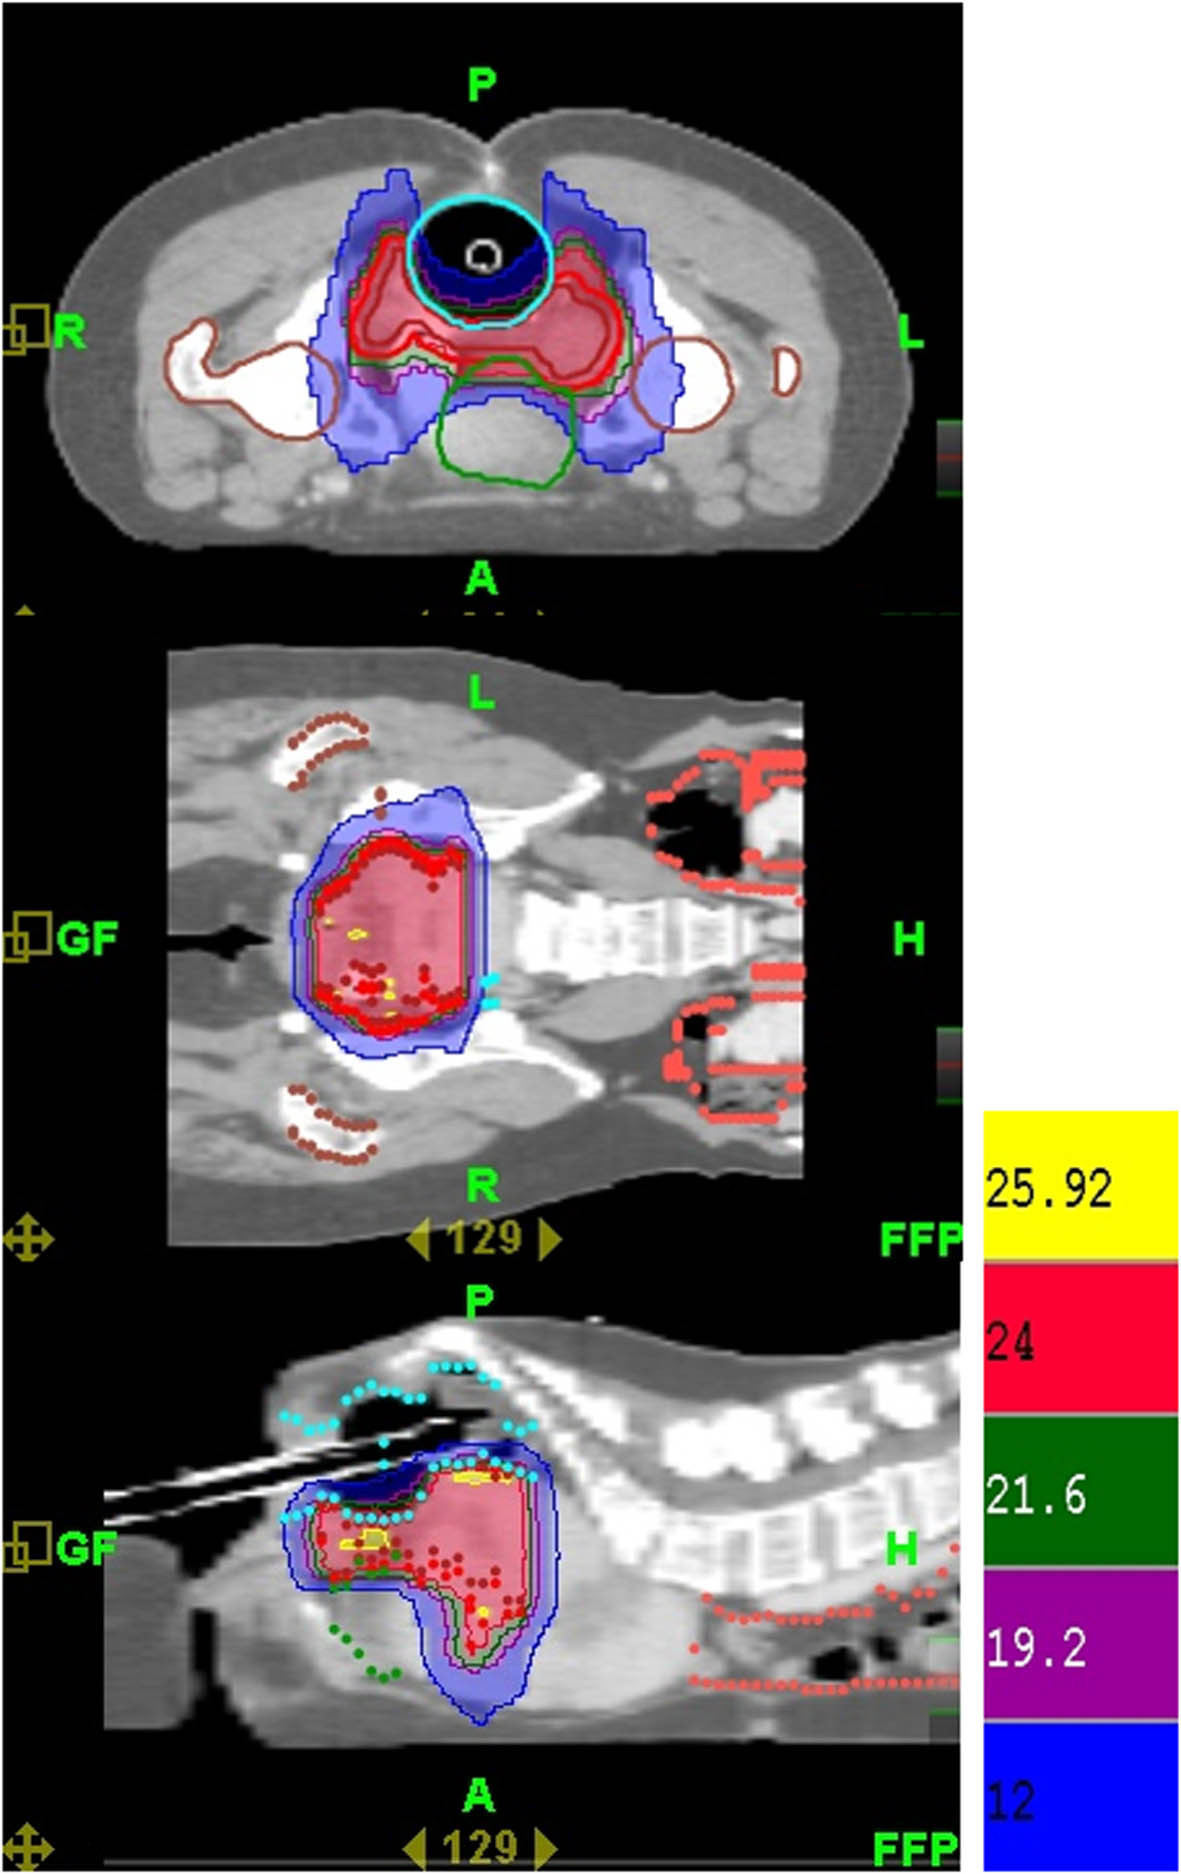

Figure 6

The dose distribution of stereotactic body radiation therapy (SBRT) for the final boost for cervical cancer.

HT-guided SBRT has been shown to be effective and well tolerated in patients with metastatic liver tumors [7], and in patients with small lung tumors [8]. In our patient, image-guided SBRT administered as a boost following CCRT resulted in a recurrence-free outcome without fistula formation at 22-month follow-up (Figure 3 and 4). However, at 14-month follow-up, the patient presented with lower GI bleeding (Figure 5). Retrospecting the planning, the conformal index [10] is 1.24. Additionally, the dose distribution has described in Figure 6. The mean dose of rectum is 45.5 Gy and the maximum dose of the rectum is 81 Gy where is close to the tumor and compatible to the bleeding area. The incidence of major late sequalae of RT for stages IIB and III of the cervix ranges from 10% to 15% [11]. Perez et al. [11] and Pourquier et al. [12] reported that with doses below 75 to 80 Gy delivered in limited volumes by a combination of external beam and intracavitary insertions with low dose rate (60 to 80 rad/hr), the incidence of grade 2 and 3 complications was less than 5%. However, with higher doses, the incidence of complications increased to 10% to 15%. In patients receiving total doses of 60 Gy to the rectum, more complications were noted [11]. Lower GI bleeding as a late complication of an external beam boost has been reported [2, 5]. Although HT has the ability to accurately identify both the exact shape and location of the tumor so as to distribute the dose as close as possible to the margin around the target, the radiation oncologist needs to monitor the maximum doses to organs at risk (OARs) around the tumor in order to minimize, if not avoid, complications.